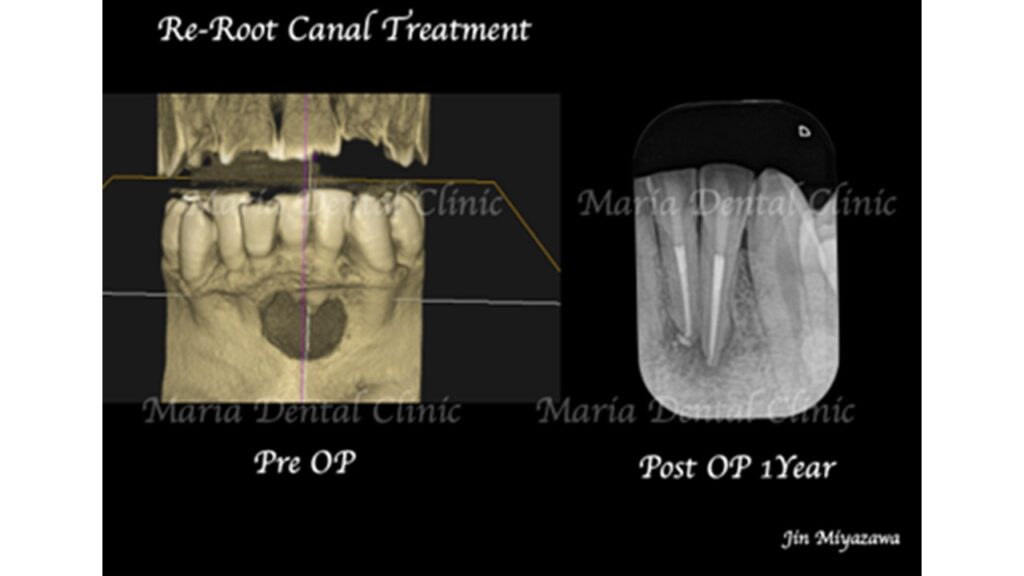

術前の写真を確認すると根の先端から広がる病変の影は歯の股の部分まで大きくなっていることが確認できます(術前写真②)

通法通り根管治療を施したことで歯ぐきの腫脹は改善したものの、分岐部(歯の股の部分)の歯周病に治癒傾向は確認されず(写真1術前)歯周病の治療に移行する判断をしました。

歯周病専門医による組織再生療法を行なった際にはレントゲンで透過像(黒い影)があった歯の股の部分の骨は著しく欠損していました(写真2術中)。骨の欠損部分に組織再生治療を行い、さらに3ヶ月の経過観察を行い生体の治癒を待ちました。

歯周組織再生療法3ヶ月後には分岐部(歯の股の部分)に確認されていた歯周病(術前写真)は完全に治癒していることを確認しました(術後3か月写真)。また同時に、術前に確認できた根尖性歯周炎も綺麗な治癒が確認できたことから最終補綴処置へ移行しました。今後最低2年間は歯肉、根尖周囲組織の治癒経過を患者様にご協力いただき確認していく予定です。